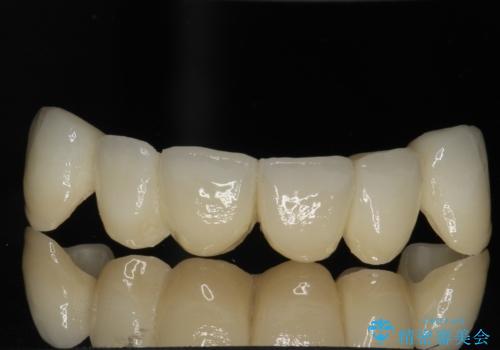

→根管治療終了後、ファイバーコアを築造し、新しいセラミックブリッジを製作した。

かぶせ物の種類:PFZ standard